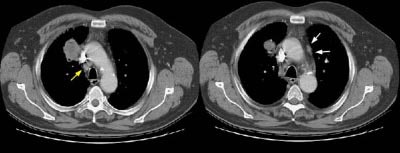

Example 1: This is an example of an N1 node in a patient with a lingular adenocarcinoma (left image). Although not pathologic by short axis size criteria, the lymphatic tissue in the left hilum has a convex border with the adjacent lung (white arrows). This node contained adenocarcinoma at histopathologic analysis. Some authors advocate using the presence of a convex margin of the interstitium with the lung parenchyma to indicate pathologic adenopathy to improve the sensitivity of CT for detecting hilar metastases [36].

Example 2: This patient is an example of a false negative CT for hilar nodal metastases even when applying the suggested new criterion. The patient had a peripheral adenocarcinoma in the left upper lobe (black arrows). The left hilar node (yellow arrows) is not pathologic by size criteria, nor does it exhibit a convex margin with the adjacent lung parenchyma. This is a normal node by CT, however, at histopathologic analysis the node was positive for malignant cells.